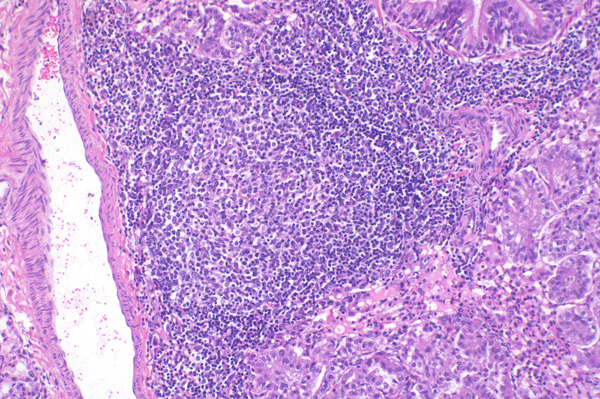

| 10x   |   Hematoxylin and Eosin | ||||

The blood vessel is surrounded by prominent lymphoid tissue that contains a germinal center (*).